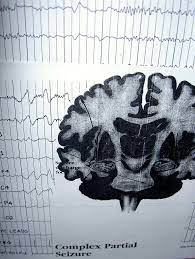

4. 뇌 전기활동 모니터링 (EEG): EEG는 뇌의 전기 활동을 측정하는데 사용되며, 발작 활동을 감지하고 기록하는 데 중요한 역할을 합니다. EEG 검사 중에는 환자에게 전극을 부착하여 뇌파를 기록합니다. 발작 활동은 EEG 패턴에 나타날 수 있습니다.